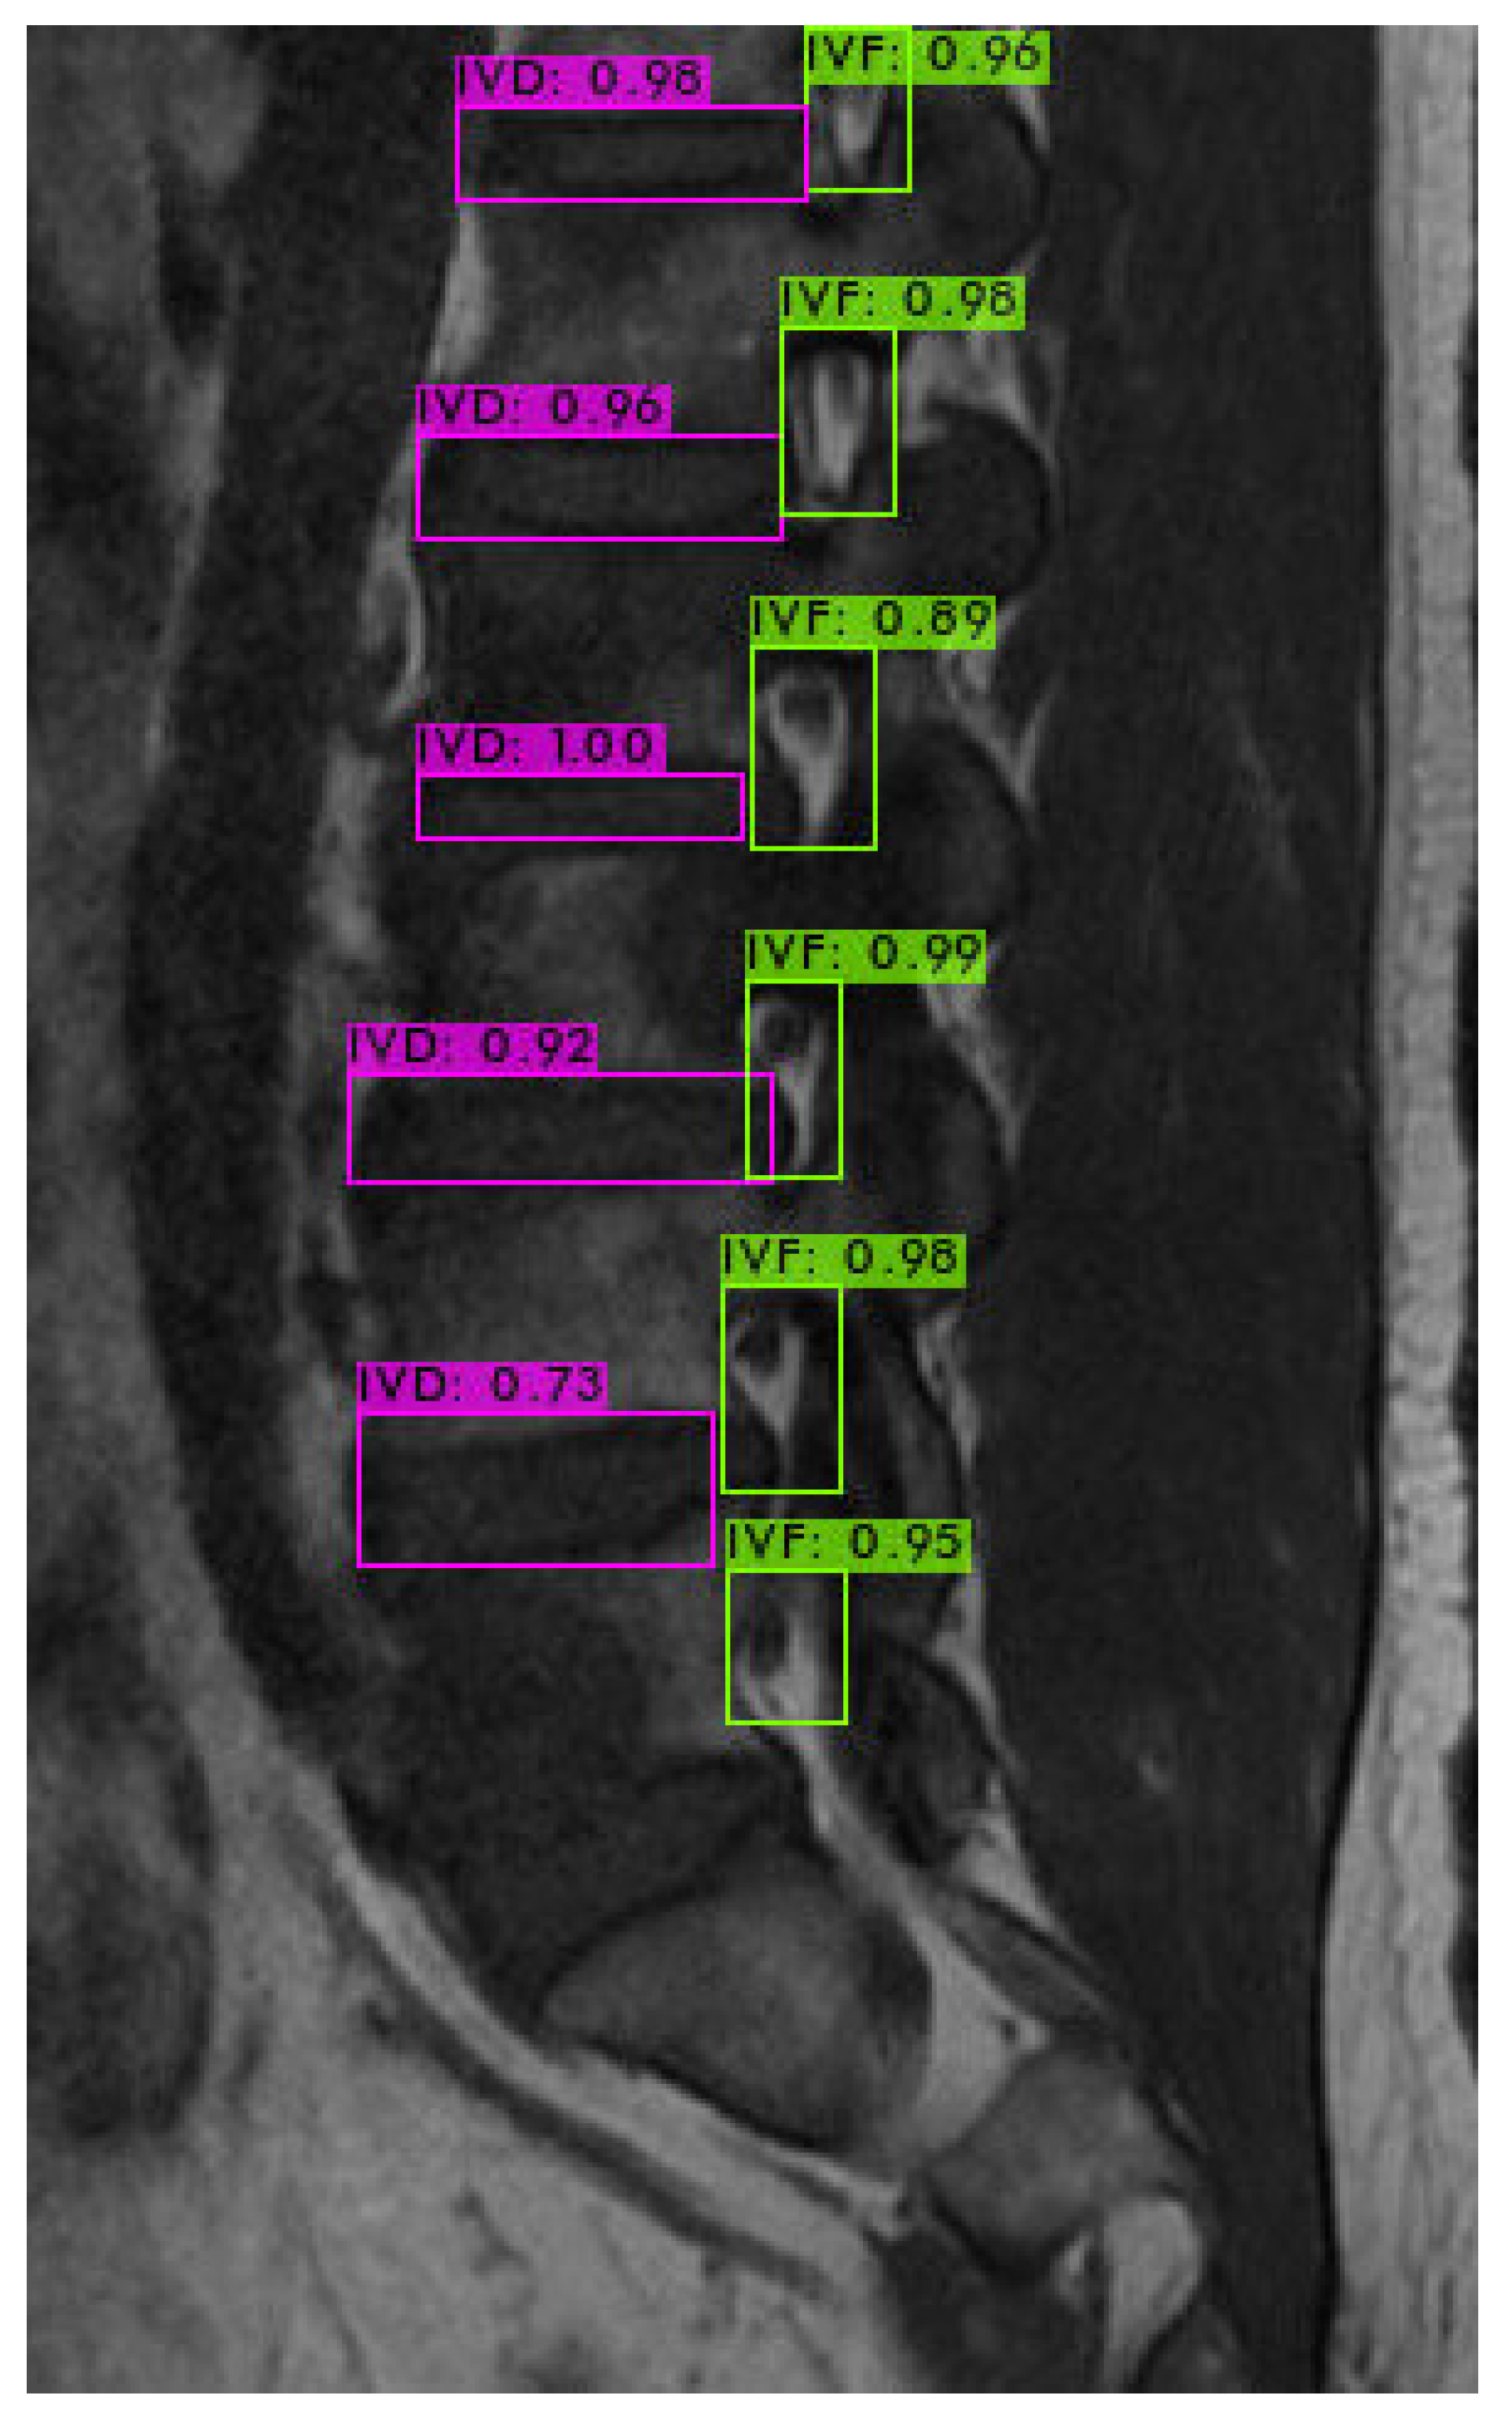

First, we used LabelImg software version v1.8.1 (https://github.com/HumanSignal/labelImg/releases, accessed on 11 February 2023) to delineate the rectangular region of the intervertebral foramen. The annotations were made in YOLO format, with the intervertebral foramen as the sole labeled class. Figure 6 shows an example of a light-green-colored annotated intervertebral foramen MRI image.

4.3. Intervertebral Foramen Identification

For identifying the area of the intervertebral foramen (IVF) and intervertebral disc (IVD), we first employ the YOLOv4 object detection model to detect the intervertebral foramen in MRI images shown in Figure 9. The detected foramen is then cropped into sub-images, which are further processed using DL methods to segment the areas of the IVF and IVD within these sub-images. After segmentation, the number of pixels occupied by the intervertebral foramen in the MRI dataset is analyzed. Finally, by using the Field of View (FOV), detailed information from the MRI dataset, this pixel count is converted into an actual area measurement in square millimeters.

Figure 6. Use LabelImg tool to annotate intervertebral foramen MRI image as green boxes.

Figure 9. YOLOv4 object detection.